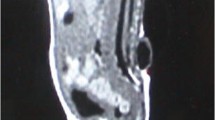

Specimens of 12 patients were analyzed in this study. Clinical characteristics were obtained retrospectively including pre-operative neurological and bowel/bladder-function, contractures and spasticity of lower extremities, leg and back pain, syringomyelia, and conus position on spinal MRI. Cellular marker expression profiles were established. Further, immunoreactivities (IR) of IL-1ß/IL-1R1, TNF-α/TNF-R1, and HIF-1α/-2α were analyzed qualitatively and semi-quantitatively by densitometry. Co-labeling with cellular markers was determined by multi-fluorescence-labeling. Cytokines were further analyzed on mRNA level. Immunostaining for cleaved PARP and TUNEL was performed to detect apoptotic cells.